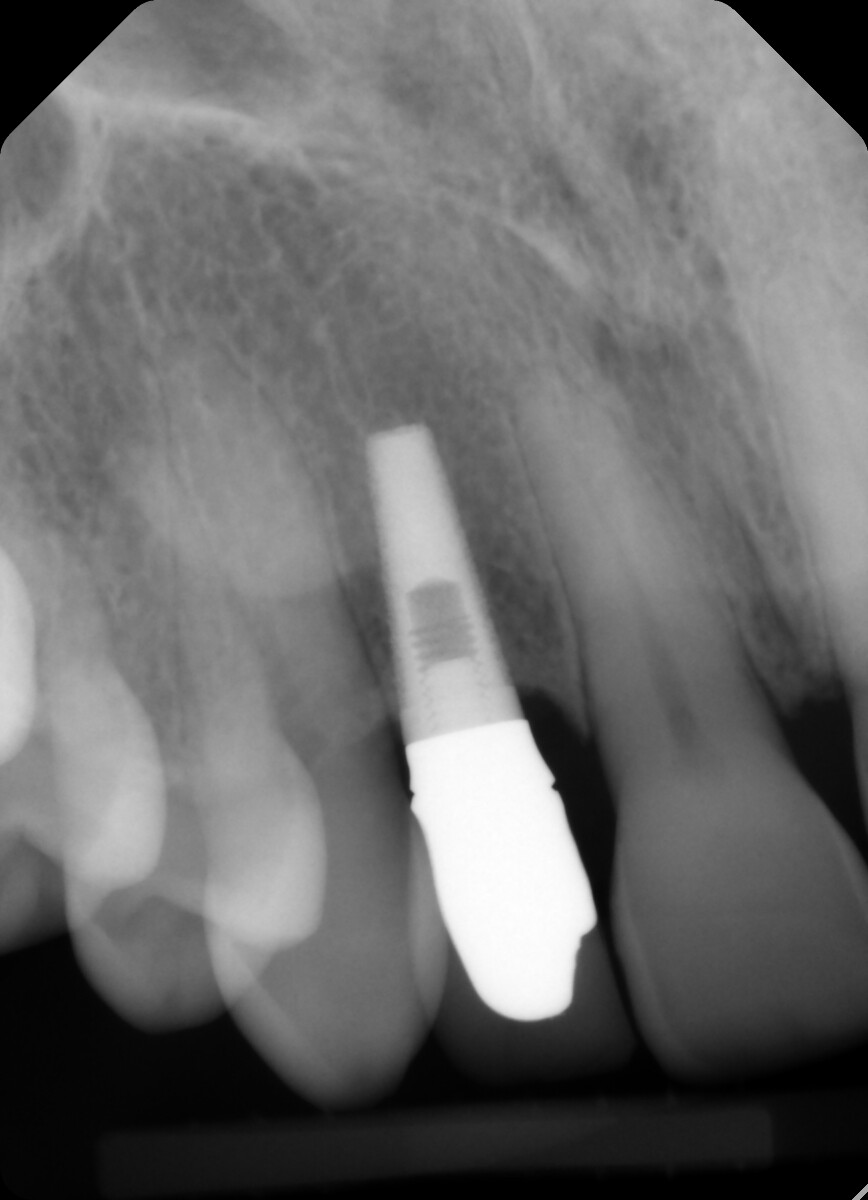

Is there any way you can remove the crown/abutment so we can see the connection. The shape of the fixture looks like it might be an Endopore. Endopore was a beaded fixture from Sybron (Innova) that was popular for a “short” period of time back in the 1990’s and early 2000’s.

This must be an Endopore implant from Innova. It was a Canadian implant that was press fit. It worked well as long as all the beaded surface remained covered in bone.

Yes, this is Innova Endopore external hex. Not sure if it’s 3.5 or 4.1 platform. Guessing 3.5 platform. You can find restorative from Titan Implants. https://titanimplants.com/innova-endopore-entegra-compatible-external-hex/